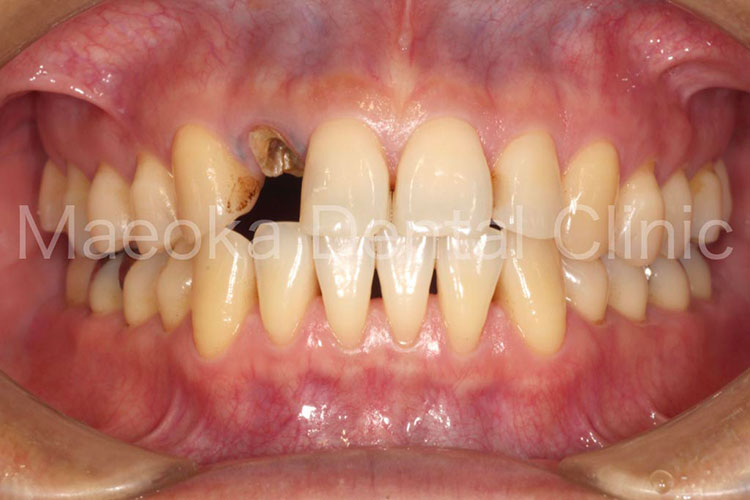

患者さんは58歳の男性の方で、「右下の歯がグラグラして痛いので診て欲しい」という主訴で来院されました。お口の中を拝見すると重度の歯周病を認めました。1日1箱近い本数の喫煙があったこともあり、歯肉は血行不良を起こして黒っぽい印象がありました。

初診時には歯周病の原因と「どうすれば歯周病は治るのか」、「再発を防ぐためには何が必要なのか」を説明し、歯磨きのトレーニングをスタートしました。その後、患者さんのプラークコントロールレベルが向上したタイミングで歯石を取り、基本治療を終えました。その後、義歯を入れるなどの機能回復も検討しましたが、患者さん自身が不都合を感じていなかった点、レントゲン上でも残存歯の負担が増加している所見が見られなかった点を考慮し、経過観察としています。

主訴の右下7は失うことになってしまいましたが、その他の歯は現在のところ1本も失うことなく経過しています。現在も喫煙はありますが、歯肉は引き締まり、健康な組織を取り戻しています。今後はメインテナンスを通してプラークコントロールレベルの維持に患者さんと取り組んでいきます。

治療前(正面)